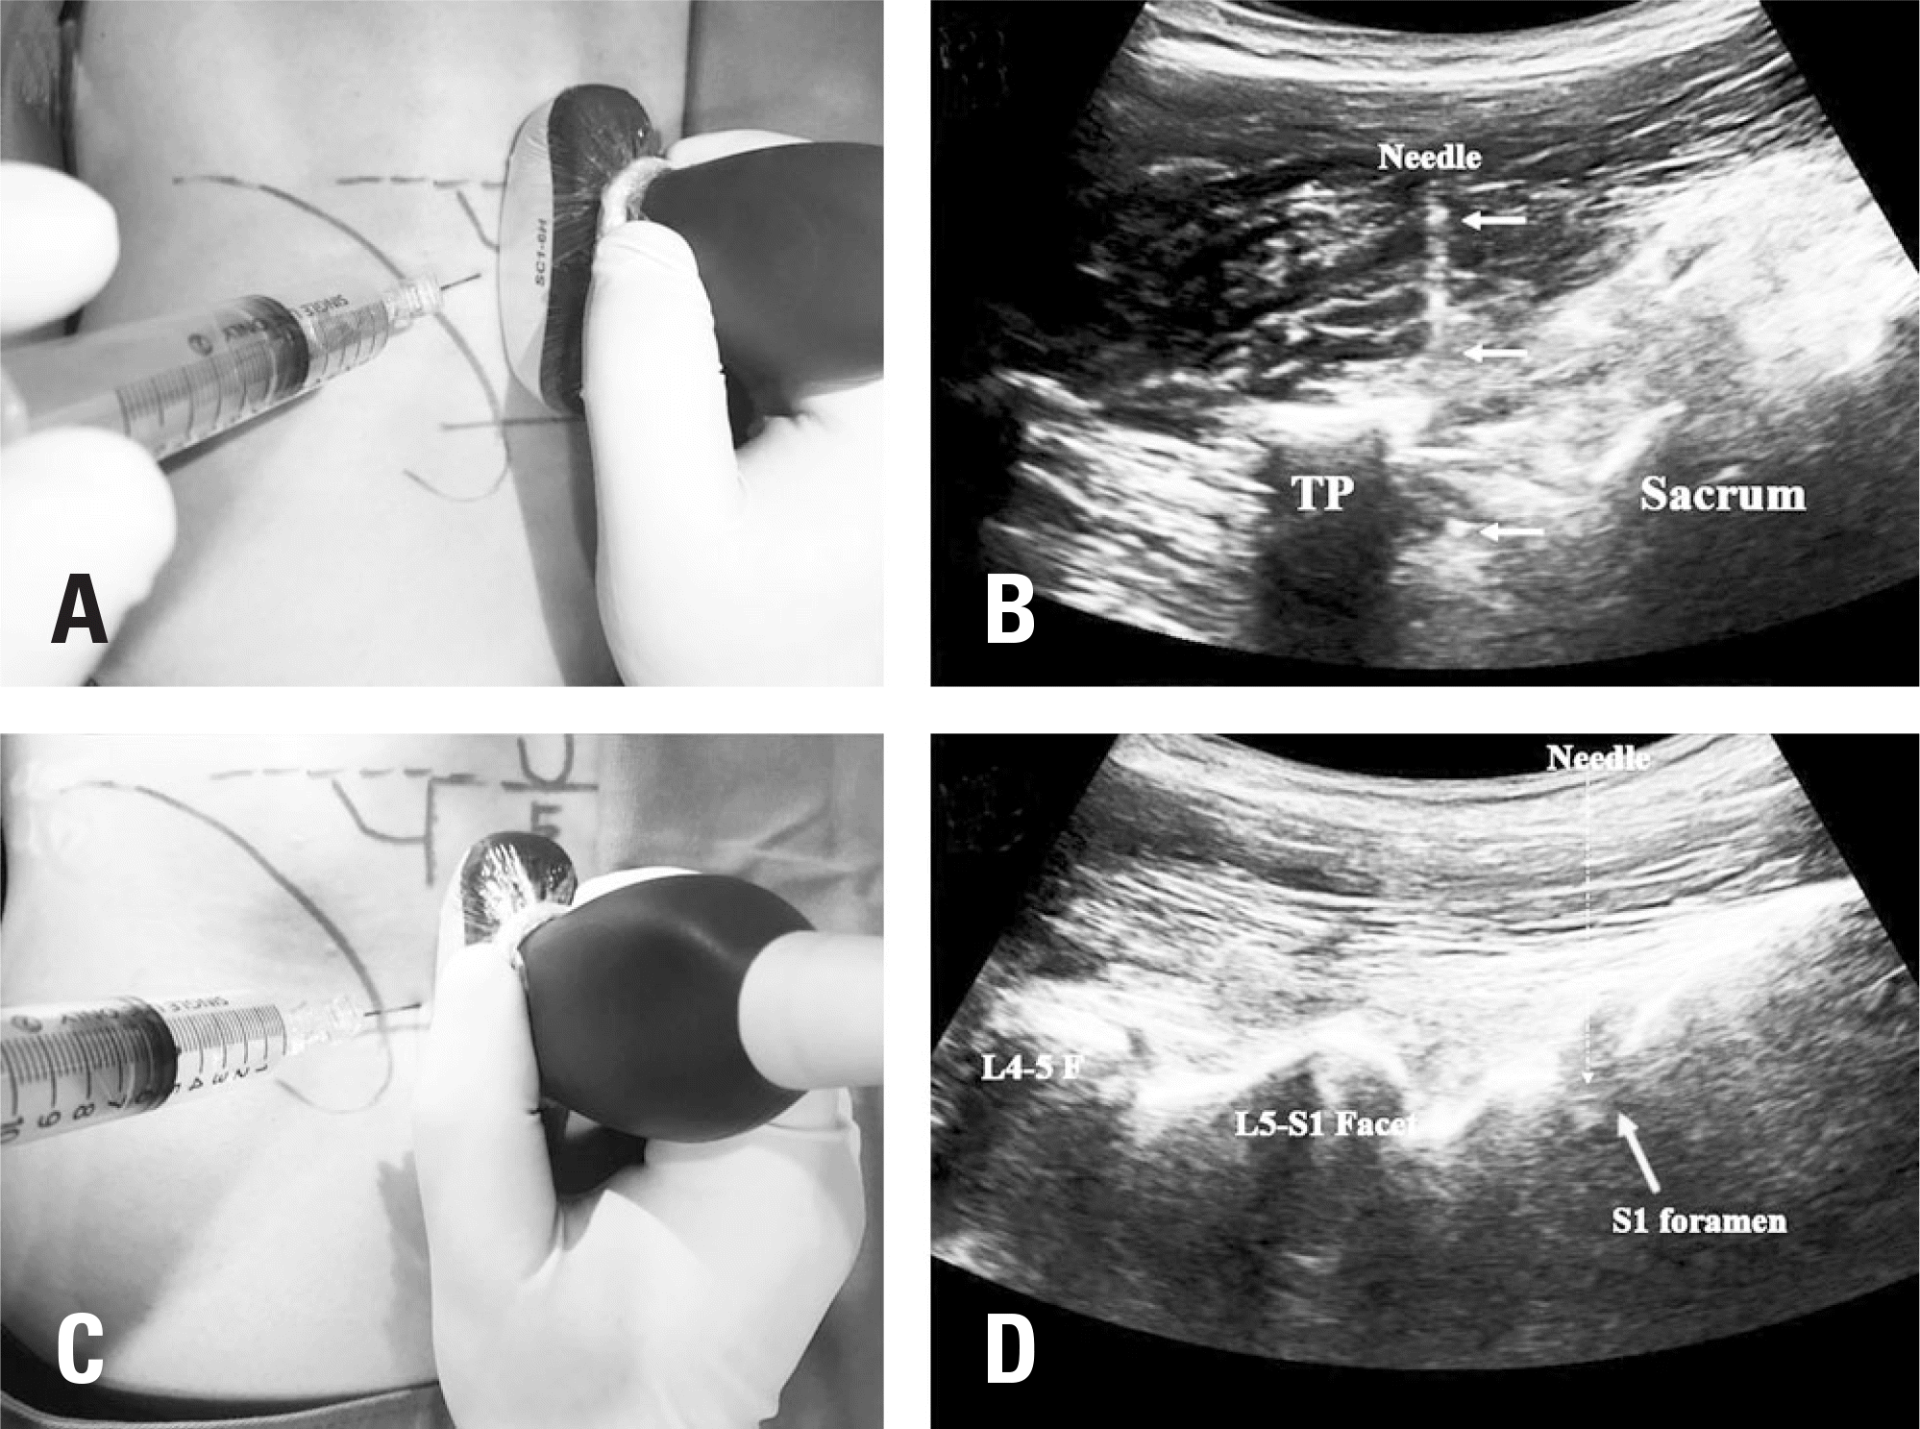

Targeted injections with mesocaine and Dopa-Medrol – precise administration of medication into the affected area under ultrasound guidance.